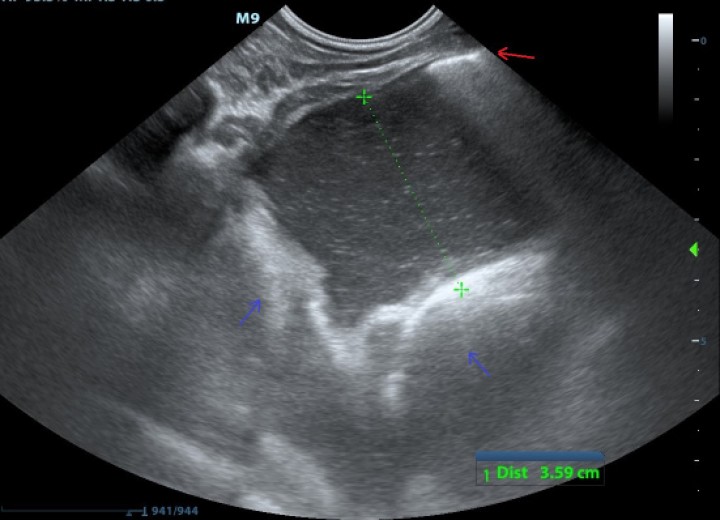

En el caso descrito se realizó una ecografía TFAST torácica (Fig. 3), en la que se observó efusión pleural moderada (material anecoico con ecos en suspensión) y colapso de lóbulos pulmonares adyacentes. Además, sirvió para monitorizar la colocación del drenaje torácico.

<p>Ecografía TFAST. Línea de reverberación compatible con signo de deslizamiento pleural (flecha roja), y espacio anecoico con ecos en suspensión, compatible con líquido pleural (punteado verde). En zonas más profundas se observa una zona pleural engrosada (flechas azules).</p>

Ecografía TFAST. Línea de reverberación compatible con signo de deslizamiento pleural (flecha roja), y espacio anecoico con ecos en suspensión, compatible con líquido pleural (punteado verde). En zonas más profundas se observa una zona pleural engrosada (flechas azules).